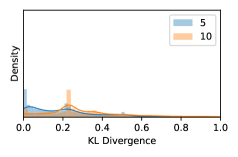

5.1 Distribution of Uncertainty Scores

Distribution of Uncertainty Scores Across Different Severity Levels As explained in Section 3, each uncertainty metric essentially defines an order/ranking among the data points. We conducted an analysis to better understand what data will be assigned high uncertainty under a particular uncertainty metric . Picking out the highest ranked data points (), we calculated the ratio of data points from each SL. Figure 4 summarizes the results as box plots for the Kaggle-DR and the Messidor-2 datasets; additional detailed statistics can be found in Table S.1 in the supplementary materials. From the plot and table, SL1 & SL2 examples account for a higher proportion among the top-ranked uncertain examples across the three ensemble methods. This finding matches our intuition that incipient disease examples (SL1 & SL2) are more likely to be considered uncertain by ensemble methods due to their ambiguity.

In contrast, the MC-dropout method showed the worst overall performance among the three, as it can be seen from the high ratios of SL0 examples among the uncertain negatives in Figure 4. The histograms in Figure 2 provides another perspective to look into the phenomenon, where a decent proportion of MC-dropout model’s predictions on SL0 inputs entailed low confidence (far from 0 or 1), which from another angle explained why MC-dropout was less specific in terms of lower FNP; many no-DR inputs (i.e. SL0) were erroneously assigned high uncertainty by MC-dropout models.

As discussed in Section 5.1 and Section 5.3 in the main paper, the mean metric and the stacking ensemble will have better performance in the precision (specificity) on the ambiguous data. Here, more detailed results are shown in Figures S.3 & S.6 and Table S.1. Figures S.3 & S.4 show the histograms of the uncertainty score for Kaggle-DR and Messidor-2 datasets that are the in-distribution (i.d.) dataset in our experiment and FigureS.5 & S.6 show the histograms for ImageNet and CIFAR-10 datasets, which is the o.o.d. datasets in our experiment. Each group of histograms contains results from the three evaluated ensemble methods (stacking ensemble, MC-dropout and TTA) and the three uncertainty metrics (mean, var and kl). Additional detailed results not displayed in Figure 4 can be found in Table S.1, which shows the proportion of the data of different SLs varies across different . For comparison, we also included in Table S.1 the results from single learners, and the proportions of data of different SLs (before any selection was made).